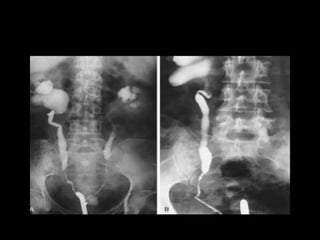

Diagnostico

Estudios de imagen

• Urografía excretora

• TAC

• Pielografía anterógrada o retrógrada

Diagnostico • Sospecharla: mecanismolesión, fiebre, • leucocitosis, irritación local peritoneal • Hematuria • Reconocimiento intraoperatorio Estudios de imagen • Urografía excretora • TAC • Pielografía anterógrada o retrógrada